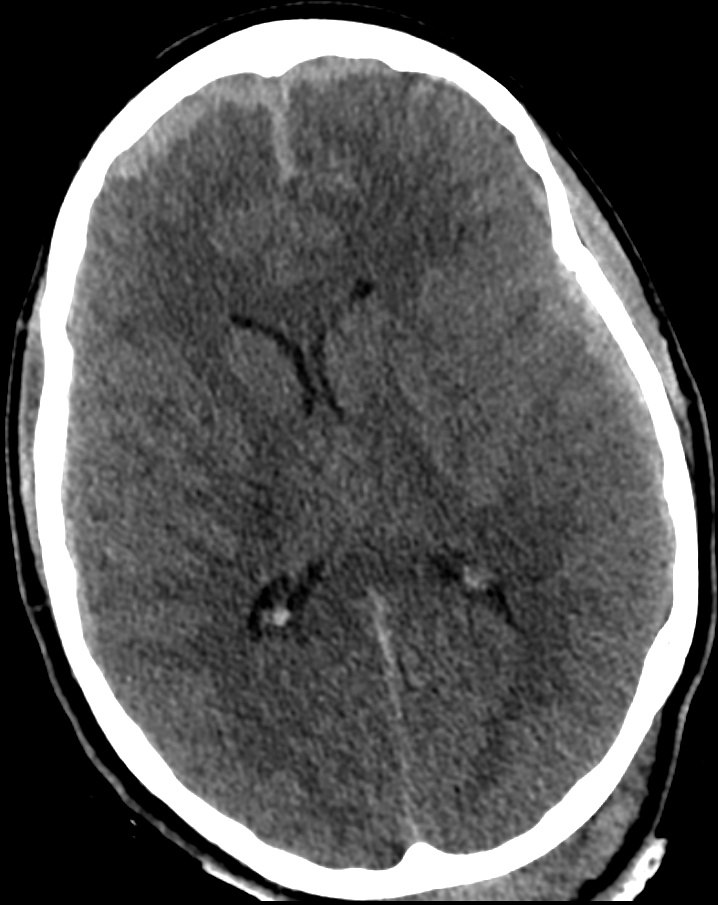

Schädelhirntrauma im CT

CT Bild eines Patienten mit einem schweren Schädelhirntrauma mit beginnendem Hirnödem und beidseitig frontalem akuten Subduralhämatom.